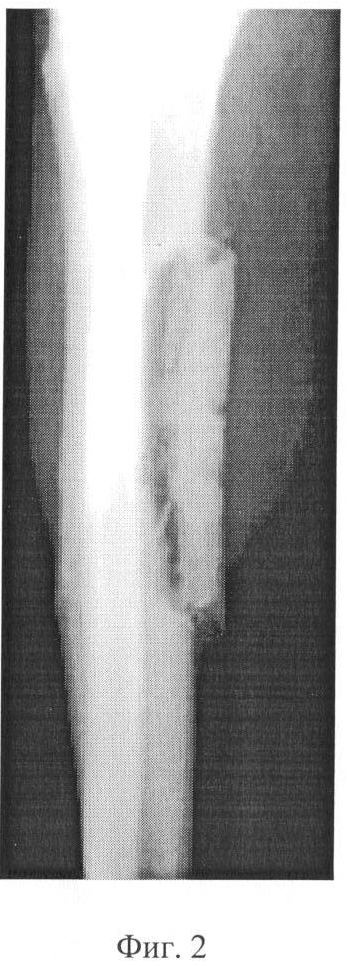

Фиг. 2 – рентгенограмма голени больного после демонтажа аппарата: сращение отщепа с костью после 35 суток аппаратной фиксации.

В послеоперационном периоде, начиная с 5 дня, производили дозированное – с темпом 0,5 мм в сутки – смещение сформированного отщепа (Фиг. 1). Продолжительность тракции составила 28 дней, после чего системы аппарата стабилизировали. Срок последующей фиксации в аппарате составил 35 дней. К указанному сроку рентгенологически выявлена картина консолидации большеберцовой кости и отщепа костным регенератом, который затем полностью оссифицировался (Фиг. 2, 3). Это позволило демонтировать аппарат на 15-20 дней раньше, чем у пациентов с аналогичной патологией при стимуляции кровоснабжения ишемизированных конечностей, методом чрескостного остеосинтеза, у которых консолидация кости отмечается лишь к 45-60 суткам.